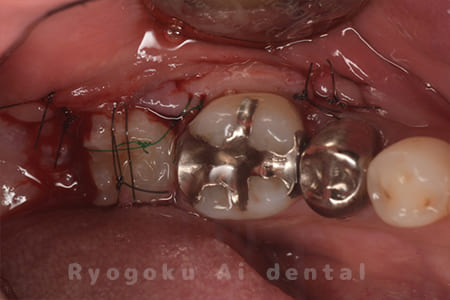

他院で右下の根の治療を行い、セラミックを被せる説明をされていたが、根の治療が終わらないため転院された患者さんです。隣の親知らずの抜歯の必要性と、根の治療を行なっている歯牙の予後が悪いため、移植治療を提案し、右下の親知らずの抜歯と同時に、右下の奥歯(7番)への移植治療を行いました。被せ物を行う必要もなく、順調に経過してます。